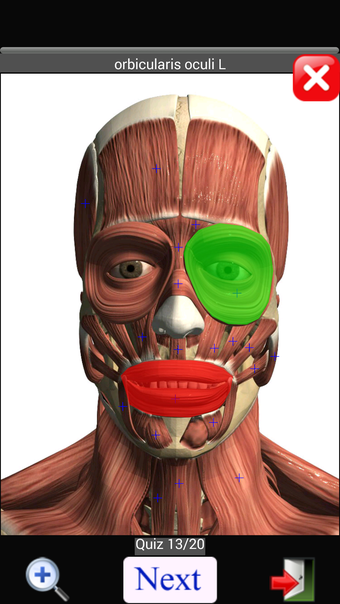

Anatomy Quiz Free es una aplicación de Android de Education Mobile que ofrece una amplia gama de cuestionarios para ayudar a los usuarios a aprender anatomía humana. La aplicación cuenta con más de 500 cuestionarios que ponen a prueba tu capacidad para identificar la ubicación correcta de un objeto dado su nombre. Los cuestionarios se generan a partir de modelos de anatomía 3D virtuales, lo que los hace más atractivos e interactivos. La aplicación es gratuita y no hay versiones premium ni compras dentro de la aplicación.

La aplicación es compatible con los idiomas inglés, francés, español y alemán, lo que la hace accesible para usuarios de diferentes partes del mundo. Las imágenes de alta resolución son nítidas y claras, y la función de zoom con pellizco te permite acercar y alejar las imágenes para una mejor vista. El cuestionario de posición viene con un temporizador, lo que lo hace más desafiante y emocionante. Además, la aplicación tiene una función de transferencia a la tarjeta SD, lo que facilita su transferencia a otros dispositivos.